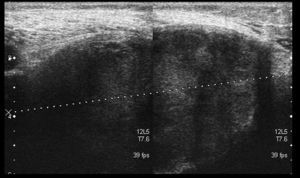

We present the case of an 83-year-old male patient with osteoarthritis, who came to the emergency room due to acute inflammation of the leg simulating DVT. On physical examination, there was a mass of elastic consistency, non-pulsatile, painful, in the popliteal fossa, extending to the leg (Fig. 1). The differential diagnosis was made with Baker cyst. The patient underwent, as a technique of choice, an ultrasound. The color Doppler mode showed patency of the deep venous system. Musculoskeletal ultrasound evidenced a well-defined collection, adjacent to the medial gastrocnemius muscle belly, full of vague echoes predominantly of low amplitude (Fig. 2) Despite being frequent, the size of the tumor made ultrasound insufficient and we decided to perform specific knee MRI with T1 potentiated sequences, T2* sequences (Figs. 3–5) and, after administration of intravenous contrast, we confirmed the existence of giant popliteal cyst of 17cm×9cm. The patient was treated conservatively, using, in the first place, nonsteroidal anti-inflammatory drugs, with clinical improvement and asymptomatic after the first 6 months. For this reason, along with the age of the patient and in spite of the cyst barely changing its size, surgical treatment has so far been dismissed.